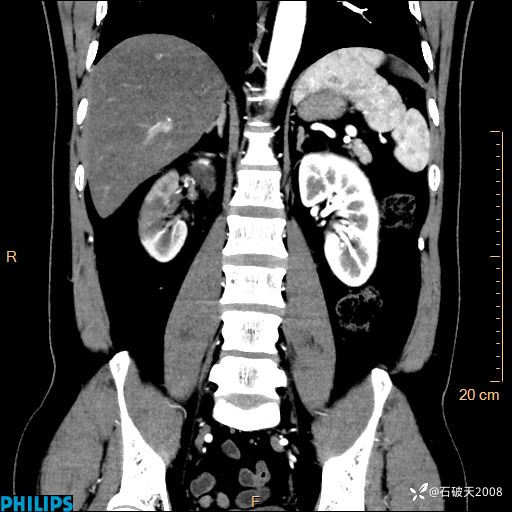

这个病例诠释了“腹部不增强,等于耍流氓”

冠状位